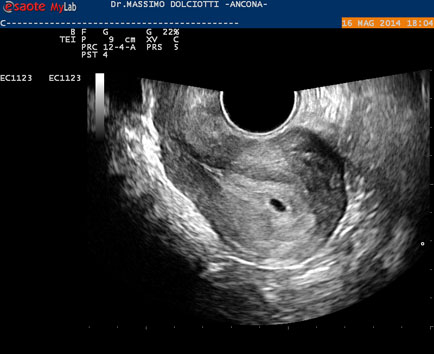

Data inserimento: 19 /05/2014Ecografia del: 16/05/2014 Strumento: Esaote MyLab 50 Gold - Responsabile Linea Cardio Esaote Regione Marche Dr. Franco Fabi Sonda: Endocavitaria Multifrequenza 4-8 MHz Età Paziente: F 27 anni Motivazione dell'esame: amenorrea. Beta HCG = 1.459 mUI/ml. Commento all'esame: le immagini ed il video documentano utero retroverso, con endometrio ispessito e presenza del sacco gestazionale delle dimensioni di 7,6 x 7,2 mm. All'ovaio destro presenza di corpo luteo gravidico con vascolarizzazione aumentata. Conclusioni: gravidanza alla quarta settimana di gestazione (Pregnancy at the fourth week of gestation). Potete esprimere le vostre osservazioni e commenti sul BLOG. Presentazione: Dr. Massimo Dolciotti - Ancona Elaborazione digitale: Andrea Dini - Ancona